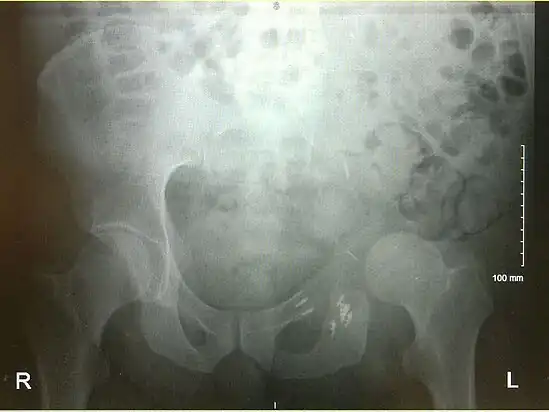

Prior to performing a hemipelvectomy, surgeons must possess detailed knowledge of the pelvic anatomy and its relation to the pelvic tumor.[1] Imaging studies such as conventional radiography, computed tomography, and magnetic resonance imaging help the surgeon visualize the anatomy and its relationship to the local pathology.[1] Surgical oncology techniques are utilized when resecting tumors of the pelvis.[1] Such techniques ensure that adequate resection margins are obtained at the time of surgery to minimize tumor recurrence.[1]

The Enneking and Dunham classification system was developed in 1978 to aid surgeons in characterizing pelvic resections.[1][3][4] This classification scheme breaks down pelvic resections into 3 subtypes: Type I, Type II, and Type III.[1][3][4] Type I resections involve removal of the ilium.[1][3][4] Type II resections involve removal of the peri-acetabular region.[1][3][4] Type III resections involve removal of the ischial and/or pubic region.[1][3]

Images